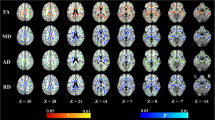

DKI data processing

The diffusion images were first transformed to NII file format by using the dcm2nii tool, then, supplied to the diffusional kurtosis estimator (DKE) to generate DKI parameter maps. The T1WI acquired by MPRAGE were supplied to the SPM12 toolbox [29]. The DWI images (b = 0 s/mm2) were strictly aligned with T1WI space, and the transformed matrix was applied to the DKI parameter map. The DKI parameters of ROIs were automatically extracted by using MATLAB (2017a, The MathWorks, Inc., Natick, MA). The parameters of DKI include: MD, AD, RD, FA, MK, AK, RK, and KFA. MK, the most commonly used DKI parameter, means the average of the diffusion kurtosis along all diffusion directions; AK is the kurtosis along the axial direction of the diffusion ellipsoid; RK is the kurtosis along the radial direction of the diffusion ellipsoid; and FA is the most commonly used DTI parameter, which has been a primary imaging metric used in the evaluation of a wide range of neuropathologic processes [30]. The cingulum (CG) in the cingulate gyrus and the hippocampal regions is separated at the axial level of the splenium of the corpus callosum and denoted as CgC and CgH, respectively. CgC and CgH were selected as ROIs according to the ICBM template (see Fig. 2) [31].